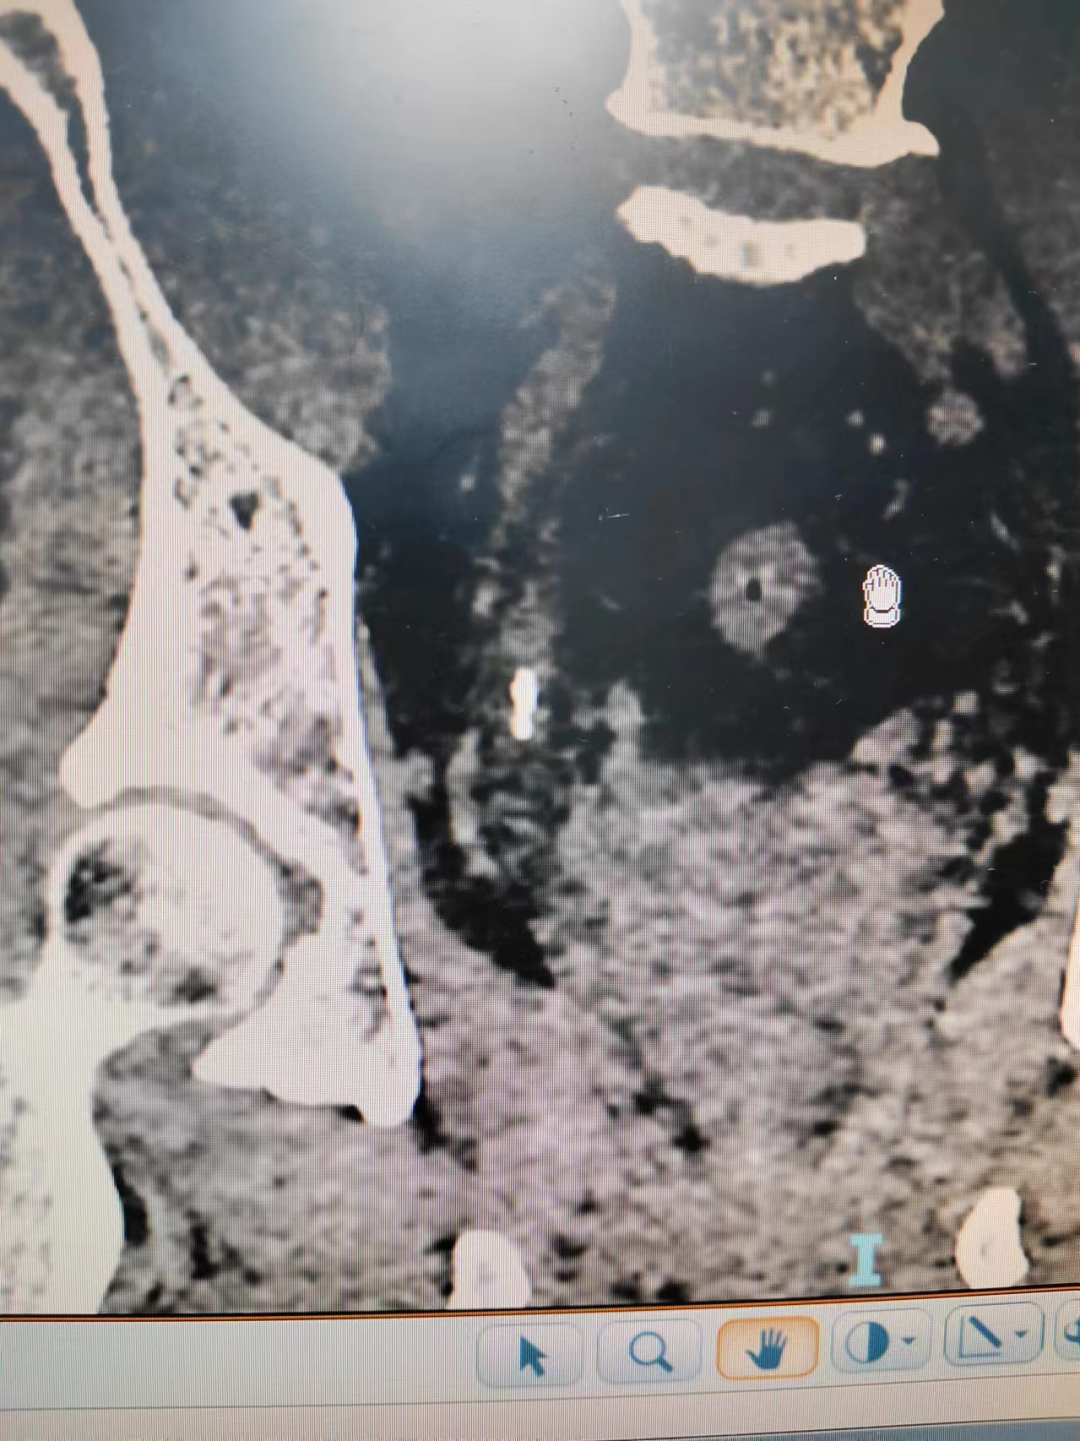

接診以后,立刻安排患者進(jìn)行CT檢查,發(fā)現(xiàn)岳先生的結(jié)石是多個(gè)結(jié)石掉落在輸尿管內(nèi),形成“石街”。造成泌尿系統(tǒng)完全性梗阻,患者肌酐已經(jīng)升高。